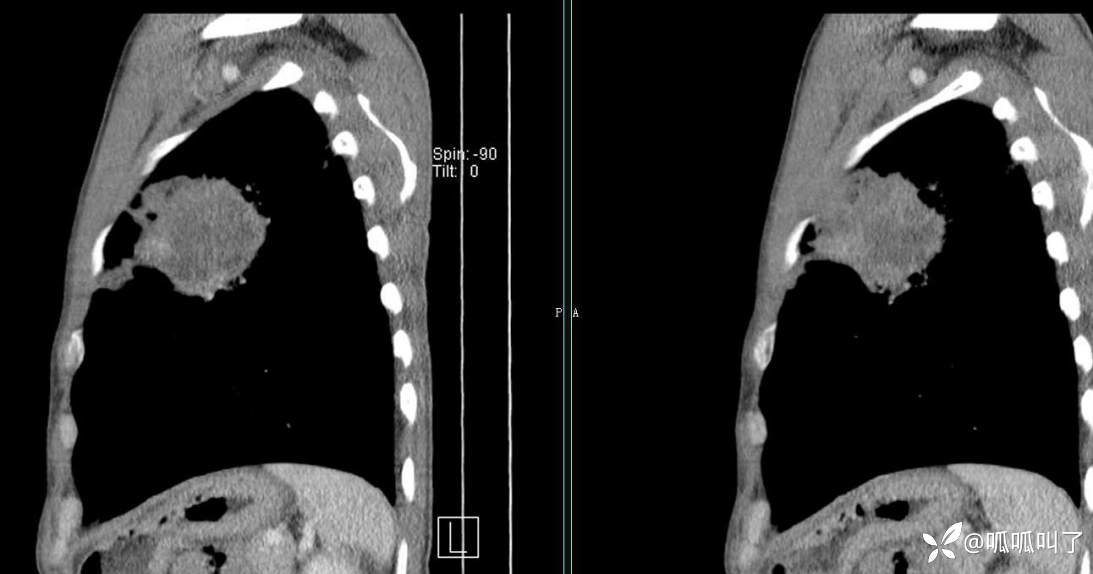

胸部CT平扫和增强: